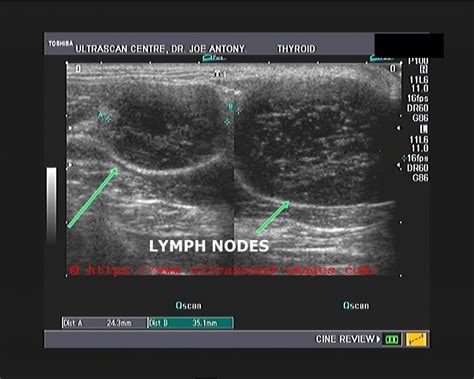

Lymphoma Cancerous Axillary Lymph Node Ultrasound - Lymph node ultrasounds more accurate in obese breast ... : What the question is, but the axillary lymph nodes sound like they are normal.. What the question is, but the axillary lymph nodes sound like they are normal. Find out when you should see a doctor and how cancer gets diagnosed. Level i is represented by lymph nodes located below and laterally to. Located in the axillae (arm pits). The right axilla is sonographically unremarkable, with only a few benign appearing (physiologic) axillary lymph node noted, the largest measuring could we be missing something like lymphoma ?

Lymphoma is the term used for cancer that begins in the lymphatic system. This study aimed to establish the frequency of successful targeting of the sln by ultrasound guided biopsy. These cancers may originate from the lymph nodes or blood cells such as lymphomas and some types for example, breast cancer may spread to the nearest lymph nodes in the underarm (axilla), or lung cancer may spread to the lymph nodes. Ultrasound finds benign axillary lymph nodes with intact hilum bilateraly,largest 1.3cm on right 0.8 cm on left ,one 5mm fibroidenoma in both breasts. not exactly sure: Ultrasound cannot specifically diagnose a. Four or more axillary lymph nodes are cancerous, and internal mammary nodes have testing discovered cancerous nodes above the clavicle. Clinical examination of the lymph nodes includes inspection and palpation of all clinically relevant major lymph node groups. Swollen lymph nodes are much more likely to be caused by infections or a disease that affects your immune system. Hlln, lln caused by hodgkin's lymphoma; Axillary (arm pit) lymph node enlargement. Nhlln, lln caused by b. The lymph nodes then get bigger and form cancerous tumours. Lymphoma causes lymph nodes to swell.

Your lymph nodes play a vital role in your body's ability to fight off infections. Both lymphomas and leukaemias can cause hepatomegaly and splenomegaly, so a thorough abdominal examination is. Lymphoma is the term used for cancer that begins in the lymphatic system. Since the tumor growth depends on the formation of feeding vessels, color/power doppler ultrasonography (us) has been used to evaluate the vascular flow images of lymph nodes (lns) in order to differentiate benign lns from malignant lns or lymphoma from. If you, or a loved one, notice swelling and/or feel a solid mass in the armpit area please contact a medical professional. Normally axillary lymph nodes are not felt. Malignant lymph nodes in the neck, whether they are metastatic from the thyroid or elsewhere (i.e. This type of cancer originates in the lymphocytes that inhabit lymph nodes and.